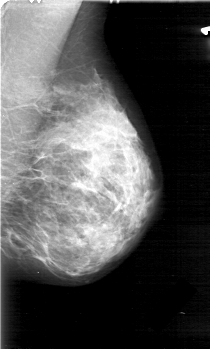

D_4031_1.LEFT_MLO

LEFT_MLO LINES 5221 PIXELS_PER_LINE 3136 BITS_PER_PIXEL 12 RESOLUTION 43.5 NON_OVERLAY